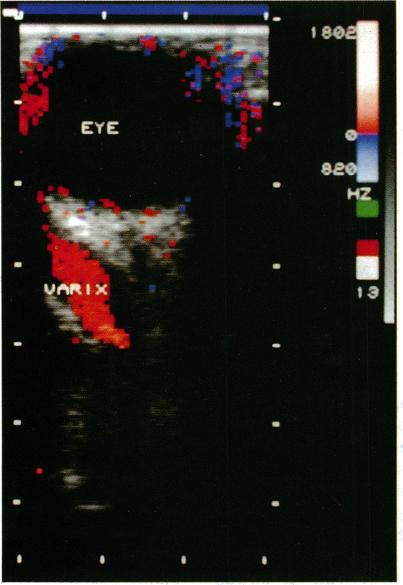

Colour Doppler imaging (CDI) is a recent development in ultrasonography. It allows simultaneous two-dimensional structural imaging and Doppler evaluation of blood flow. Quantitative information on flow velocity is obtained by pulsed Doppler spectral analysis, the colour information being used to choose the vessel of interest. Using this technique the authors examined a patient with an orbital varix previously diagnosed by clinical findings and computed tomography. Dynamic evaluation with real-time direct imaging of flow facilitated the diagnosis of this orbital disorder without the need for any contrast material. This technique may prove to be a useful adjunct to computed tomography for the evaluation of suspected vascular lesions of the orbit.

彩色多普勒成像(CDI)是超声检查领域的一项最新进展。它能够同时进行二维结构成像以及对血流进行多普勒评估。通过脉冲多普勒频谱分析可获取有关流速的定量信息,颜色信息则用于选择感兴趣的血管。作者运用这项技术对一名先前经临床检查和计算机断层扫描诊断为眼眶静脉曲张的患者进行了检查。通过对血流进行实时直接成像的动态评估,无需使用任何造影剂即可辅助诊断这种眼眶疾病。这项技术可能会被证明是计算机断层扫描在评估可疑眼眶血管病变时的一项有用辅助手段。